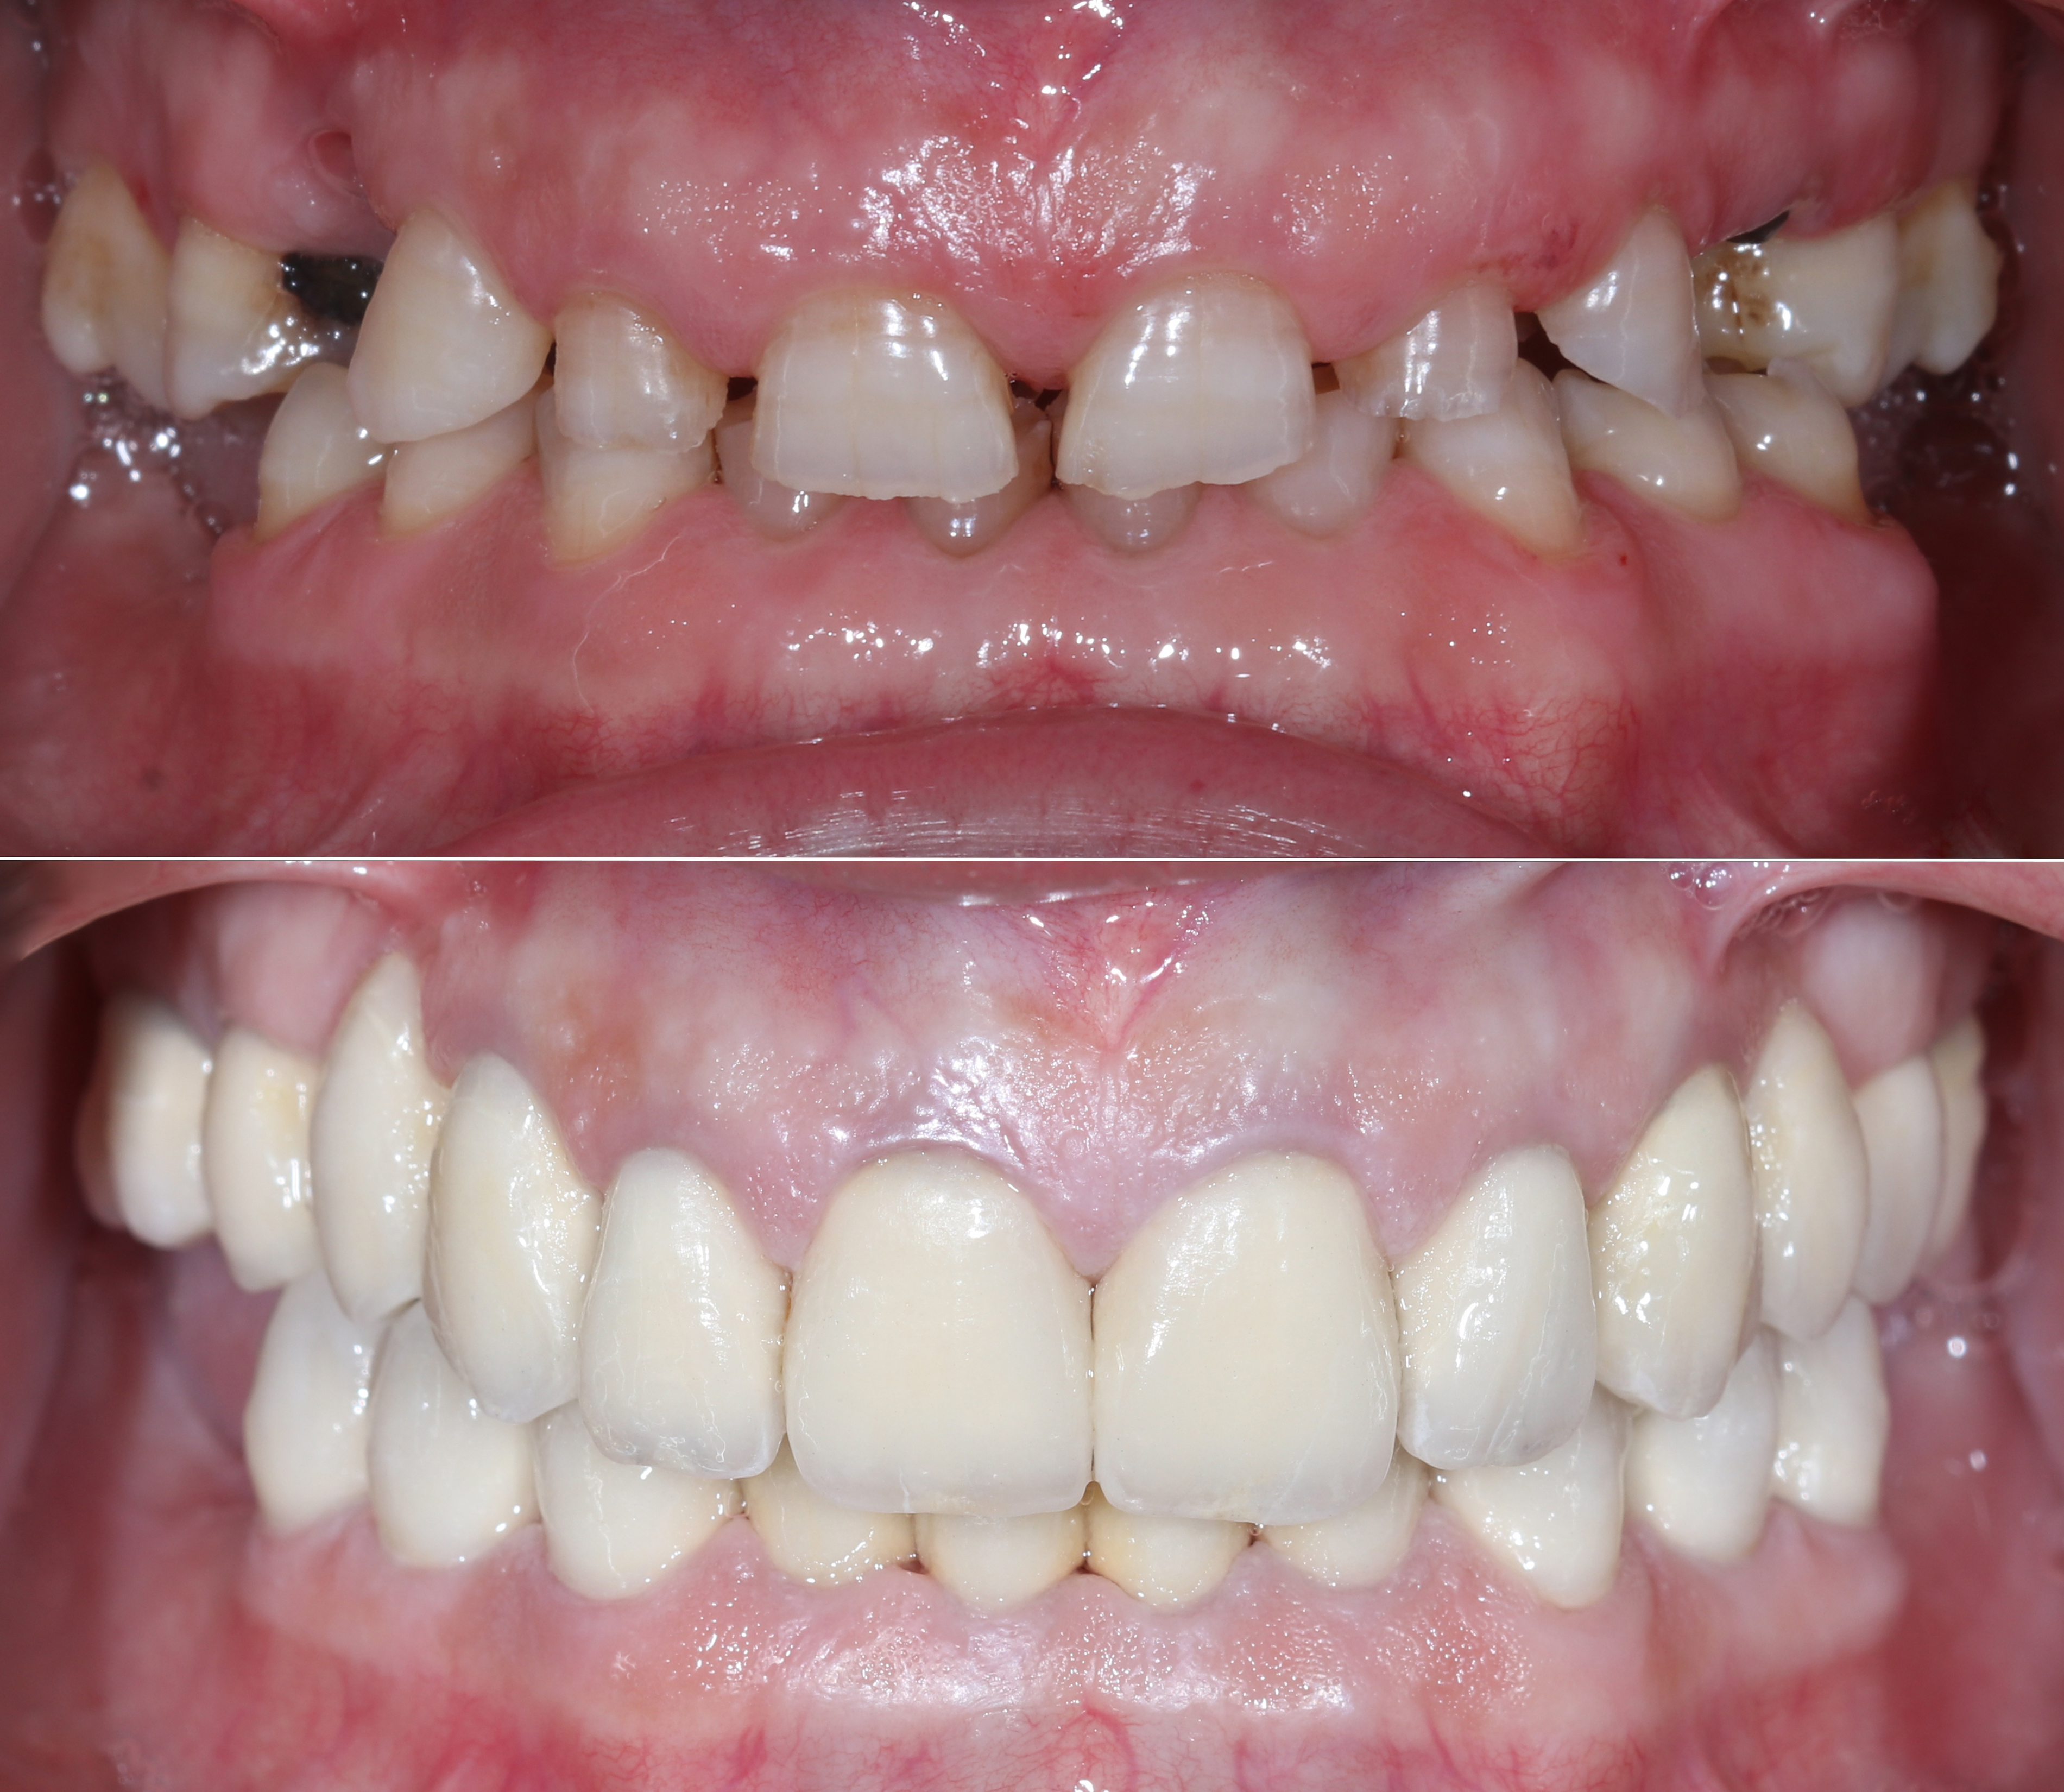

Ολική αποκατάσταση φθαρμένης και αποδιοργανωμένης οδοντοφυΐας με κεραμικές αποκαταστάσεις

Ασθενής με αποδιοργανωμένη, εκτενώς φθαρμένη οδοντοφυΐα, τερηδόνες και κατεστραμμένα δόντια στην άνω γνάθο που προκαλούσαν έντονους πόνους, προσήλθε στο Aesthetic Dental Studio στην Καλαμάτα με στόχο την αισθητική και λειτουργική αποκατάσταση του στόματός της.

Αφού όλα επιβεβαιώθηκαν, έγινε λήψη ψηφιακών αποτυπωμάτων με ενδοστοματικό σαρωτή και στην συνέχεια τοποθετήθηκαν ακίνητες κεραμικές αποκαταστάσεις ολικής επικάλυψης (στεφάνες και γέφυρες).

Το τελικό αποτέλεσμα ήταν αισθητικά άρτιο και λειτουργικά σταθερό, προσαρμοσμένο στις ανάγκες της ασθενούς.